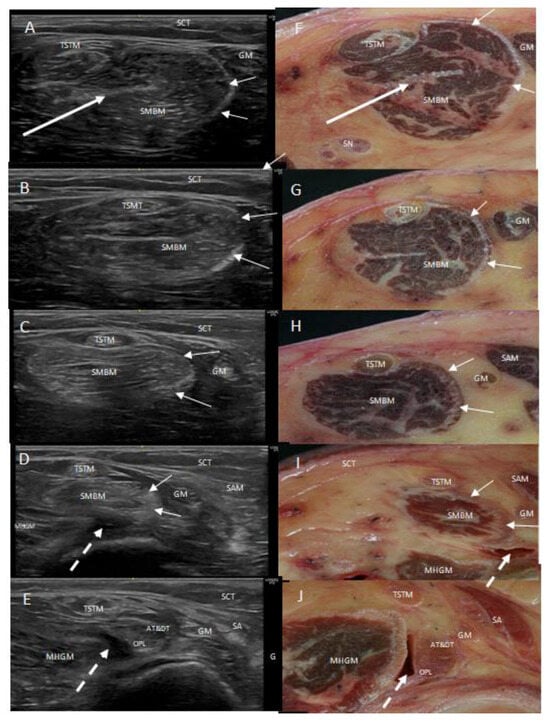

3.1. Ultrasound Study

3.2. Anatomical Study